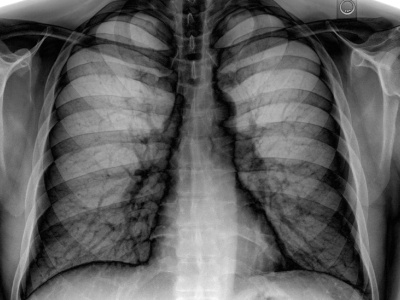

Czy można przeprowadzić badanie, które pozwoli zajrzeć głęboko w ludzkie ciało z nieosiągalną dotąd precyzją? Autorzy ostatnich postępów w tej materii twierdzą, że to możliwe – i to bez większych komplikacji, co oznacza, iż można byłoby prowadzić takie działania na masową skalę. Naukowcom udało się...